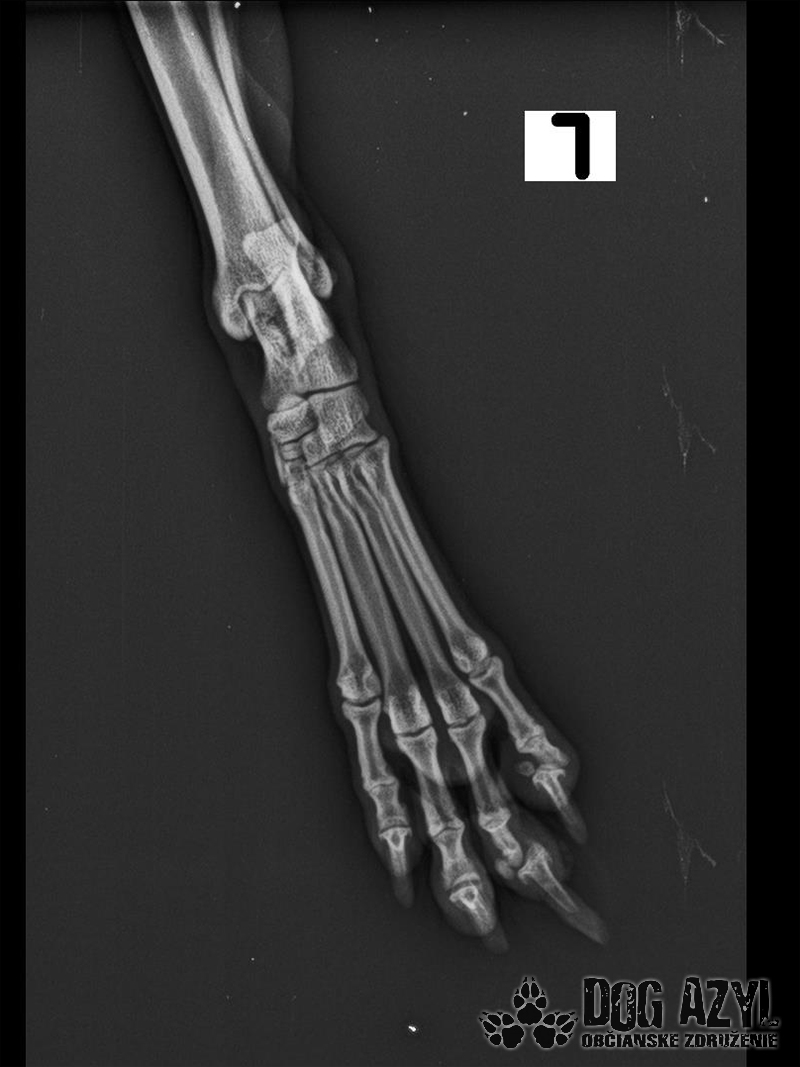

Bola neskutočne zanedbaná, hladná a dolámaná. Panvu má zlomenú na troch miestach, od úderu jej praskol močový mechúr a mala na sebe snáď všetky blchy sveta, žrali ju zaživa. Zotavuje sa.. Pomaličky, ale zotavuje sa po náročných operáciách a dúfame, že bude opäť v poriadku. Bude potrebovať rehabilitovať, aby vedela opäť behať, ale zabezpečíme jej úplne všetko, čo bude treba!!